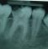

Poza Endodontie

1. Terapie endodontica

Endodontia este ramura stomatologiei car ..